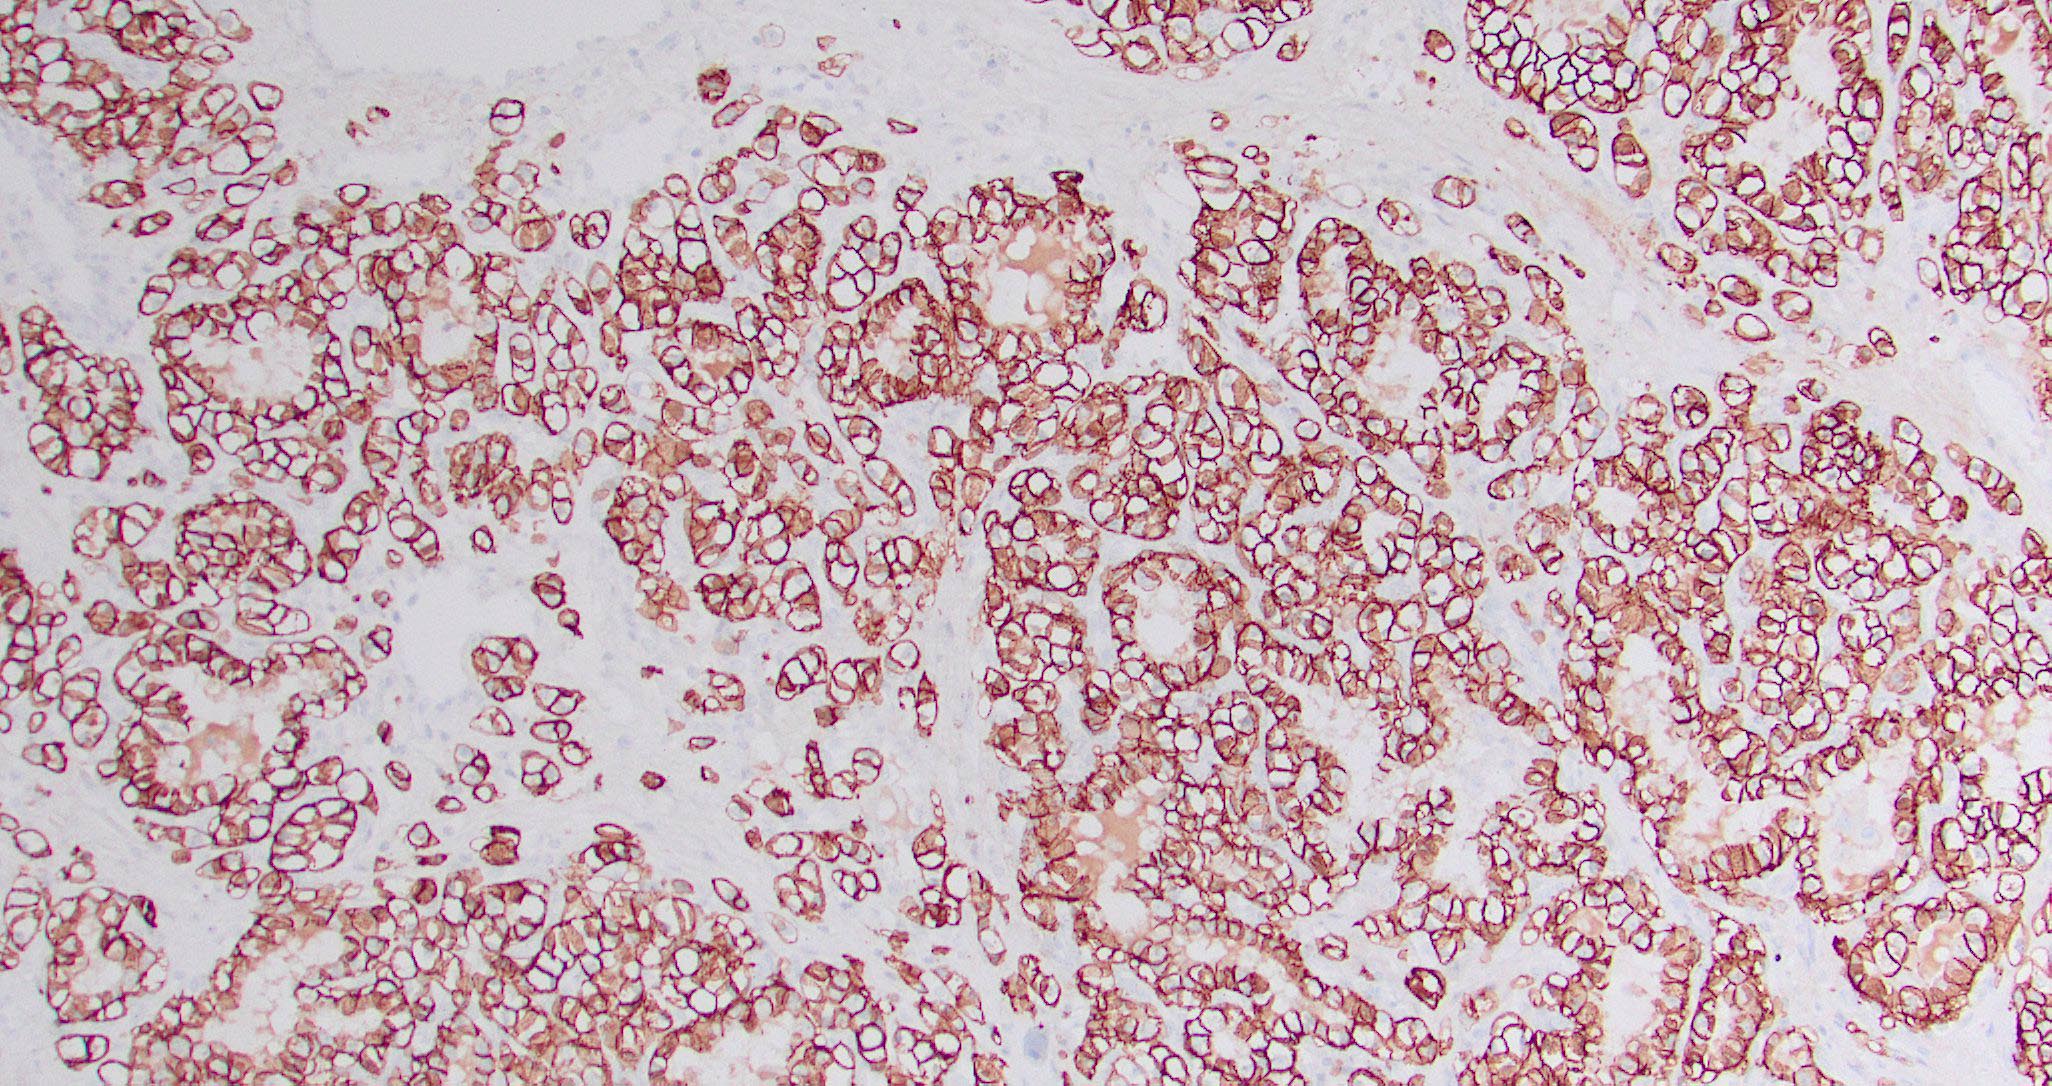

- Sinonasal renal cell-like adenocarcinoma (SRCLA) is a recently described (first case in 2002) subtype of low grade non-ITAC

- SRCLA exhibits uniform, cuboidal to polyhedral glycogen rich cells with clear cytoplasm that lacks mucin production (Head Neck Pathol 2016;10:68)

Microscopic (histologic) images

Contributed by Diana Bell, M.D.

Intestinal adenocarcinoma (ITAC)

Nonintestinal adenocarcinoma (non-ITAC)

Sinonasal renal cell-like adenocarcinoma

Positive stains

- Intestinal type adenocarcinoma

- Nonintestinal type adenocarcinoma

- Sinonasal renal cell-like adenocarcinoma

- Reference: Head Neck Pathol 2016;10:68

Negative stains

- Nonintestinal type adenocarcinoma

- Sinonasal renal cell-like adenocarcinoma

- Reference: Head Neck Pathol 2016;10:68